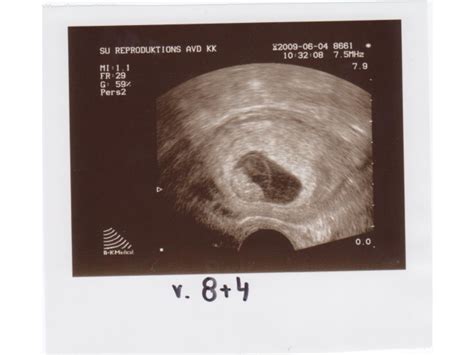

Bebis vecka 8

Gravid vecka 8 ultraljud Bebis: I vecka 8 är embryot 13 millimeter. När du är gravid i vecka 8–10 börjar embryot anta mänskliga former. De stora organsystemen såsom magtarmkanalen, njurarna och lungorna anläggs. Sakta men säkert börjar hjärnan att växa och utvecklas – likväl de inre organen som njurarna, magsäcken och tarmarna samt det centrala.

Gravid vecka 8 svullen mage Graviditeten vecka för vecka Gravid i vecka 8 (från 7 hela veckor + 0 dagar till 7 hela veckor + 6 dagar) Embryot är ungefär en och en halv centimeter långt i slutet av veckan. Än så länge mäts längden som en rak linje från huvudet till stjärten. Nu kan embryot göra enkla rörelser. Armen har fått en armbåge. På händerna börjar fingrarna växa.